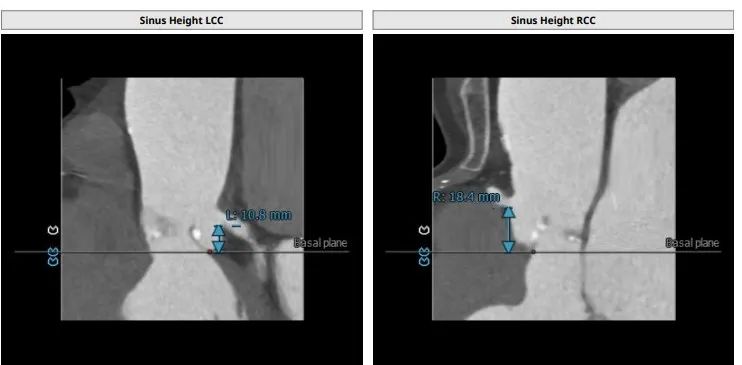

根部解剖: